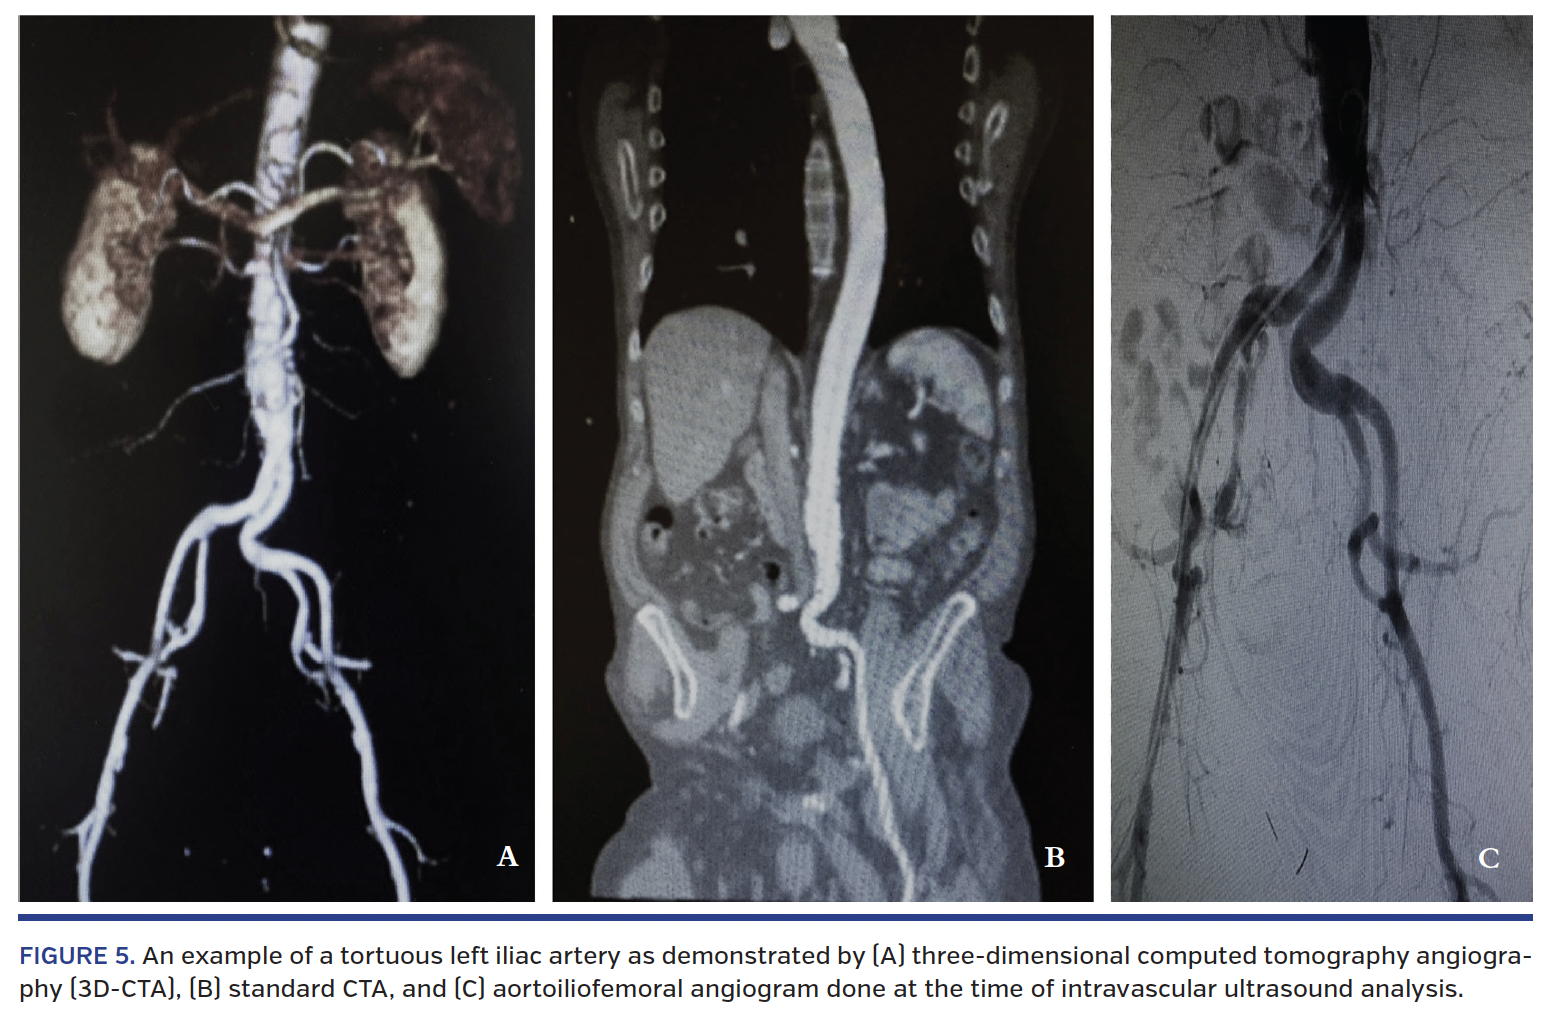

Figure 4 illustrates an example of 3D-CTA and IVUS at different segments in a single vessel. Figure 5 illustrates a severely tortuous left iliac artery as demonstrated by 3D-CTA and pre-IVUS iliofemoral angiogram.